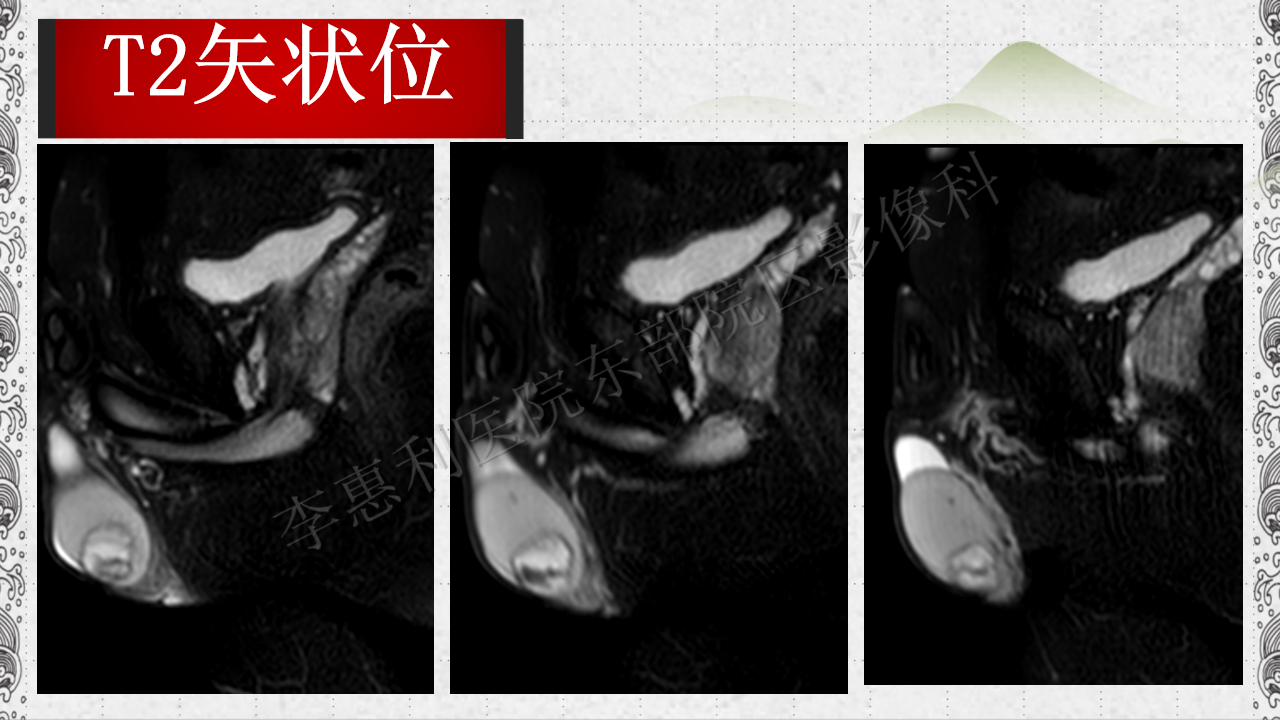

睾丸表皮样囊肿